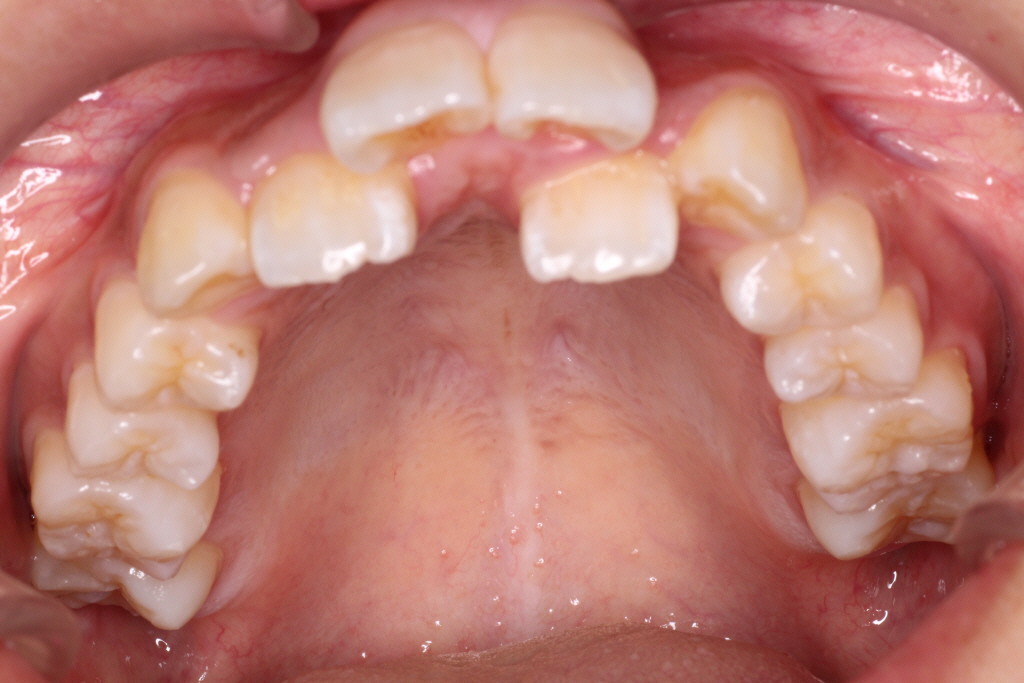

初診時のお口の中の状態です。

上の前から2番目の歯が下の歯列より内側にあり叢生です。

側方の上下の咬合関係が理想の上1本に対して下2本の理想的な噛み合わせではない。

歯列の幅がせまい。

診断:上顎前突・前歯部叢生